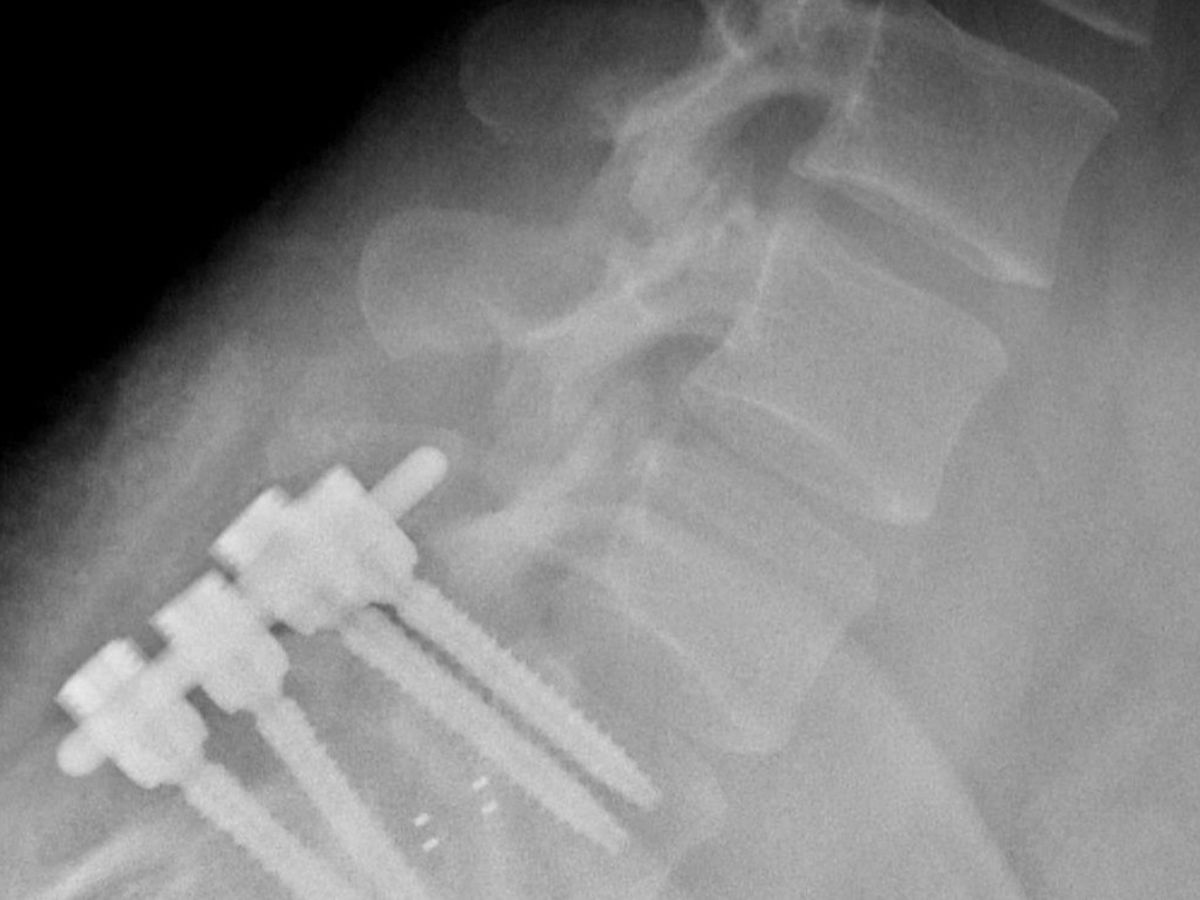

In February 2018, as I was driving to work, I was sideswiped on the highway and impacted a retaining wall, totaling my project car and seriously exacerbating my health problems. Over time, I would lose the feeling in my legs to the point of not being able to drive or walk more than a few feet at a time, and then things got worse. My spine began to deteriorate and crumble in on itself. The pain became unbearable after toughing it out as long as possible, and on February 21, 2019, I had surgery to repair the serious spinal fractures that I have accrued. As you can see in the image provided, I have four screws and two rods newly implanted in my back, and they are pretty much the only reason that I can walk upright.